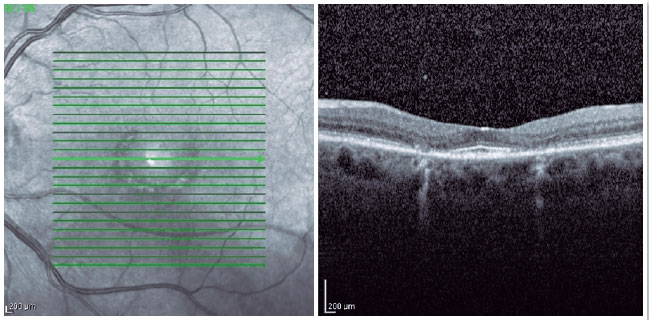

Ophthalmologic examination revealed a 20/30 visual acuity for the right eye (refraction: +1.25 SPH -0.75 CYL 45º) and 20/25 for the left eye (refraction: +0.50 SPH -0.75 CYL 10º). Biomicroscopy revealed the presence of 2+/4+ nuclear cataract in both the eyes. No further changes were observed. Fundoscopy revealed an optic disk of normal color, sharp edges, vessels with preserved caliber and path, and semicircular hypopigmented macular lesions in both the eyes, which were larger and more evident in the left eye, with a typical bull's eye maculopathy pattern (Figures 1A and 1B). Fundus autofluorescence showed semicircular hypoautofluorescent macular lesions in both the eyes (Figures 2A and 2B). Furthermore, 10-2 computerized campimetry indicated semicircular paracentral scotomas in both the eyes, larger in the left eye (Figures 3A and 3B). In addition, OCT of both the eyes revealed a flattened foveal profile, with loss of the photoreceptor inner segment/outer segment (IS/OS) junction in the perifovea and perifoveal thinning of the outer retina. Below the center of the fovea, the outer retina remained intact, resulting in an ovoid appearance. This OCT finding was is known as "the flying saucer sign" (Figures 4 and 5). Moreover, fluorescein angiography of both the eyes revealed ring hyperfluorescence, representing a circular window defect, which corresponded to the bull's eye lesion (Figures 6A and 6B).

Figure 4. Right-eye OCT with a flattened foveal profile showing the flying saucer sign with loss of the photoreceptor inner segment/outer segment (IS/OS) junction in the perifovea and perifoveal thinning of the outer retina. Below the center of the fovea, the outer retina remained intact, resulting in an ovoid appearance.

Figure 5. Left-eye OCT presenting the same changes mentioned for the right eye.

The most important methods for the diagnosis of patients and their follow-up are 10-2 computerized campimetry and OCT3. The patient may present paracentral scotoma as an early change in the visual field; this finding may precede the visual acuity decrease and the eye fundus changes. In Asian patients, a 30-2 visual field should ideally be used because they may have extramacular involvement3. The first change in spectral-domain OCT is in the ellipsoid zone, with a diminished number and thickness of the parafoveal photoreceptors. At this stage, there is no classic bull's eye lesion in the fundus, which means this finding can precede fundoscopic changes. If the use of drug is discontinued at this stage, the condition may cease to progress; however, if there is RPE involvement, it will progress. Another possible OCT finding is the flying saucer sign, which indicates the loss of the photoreceptor inner segment/outer segment (IS/OS) junction in the perifovea and perifoveal thinning of the outer retina5. Below the center of the fovea, the outer retina remains intact, resulting in an ovoid appearance.